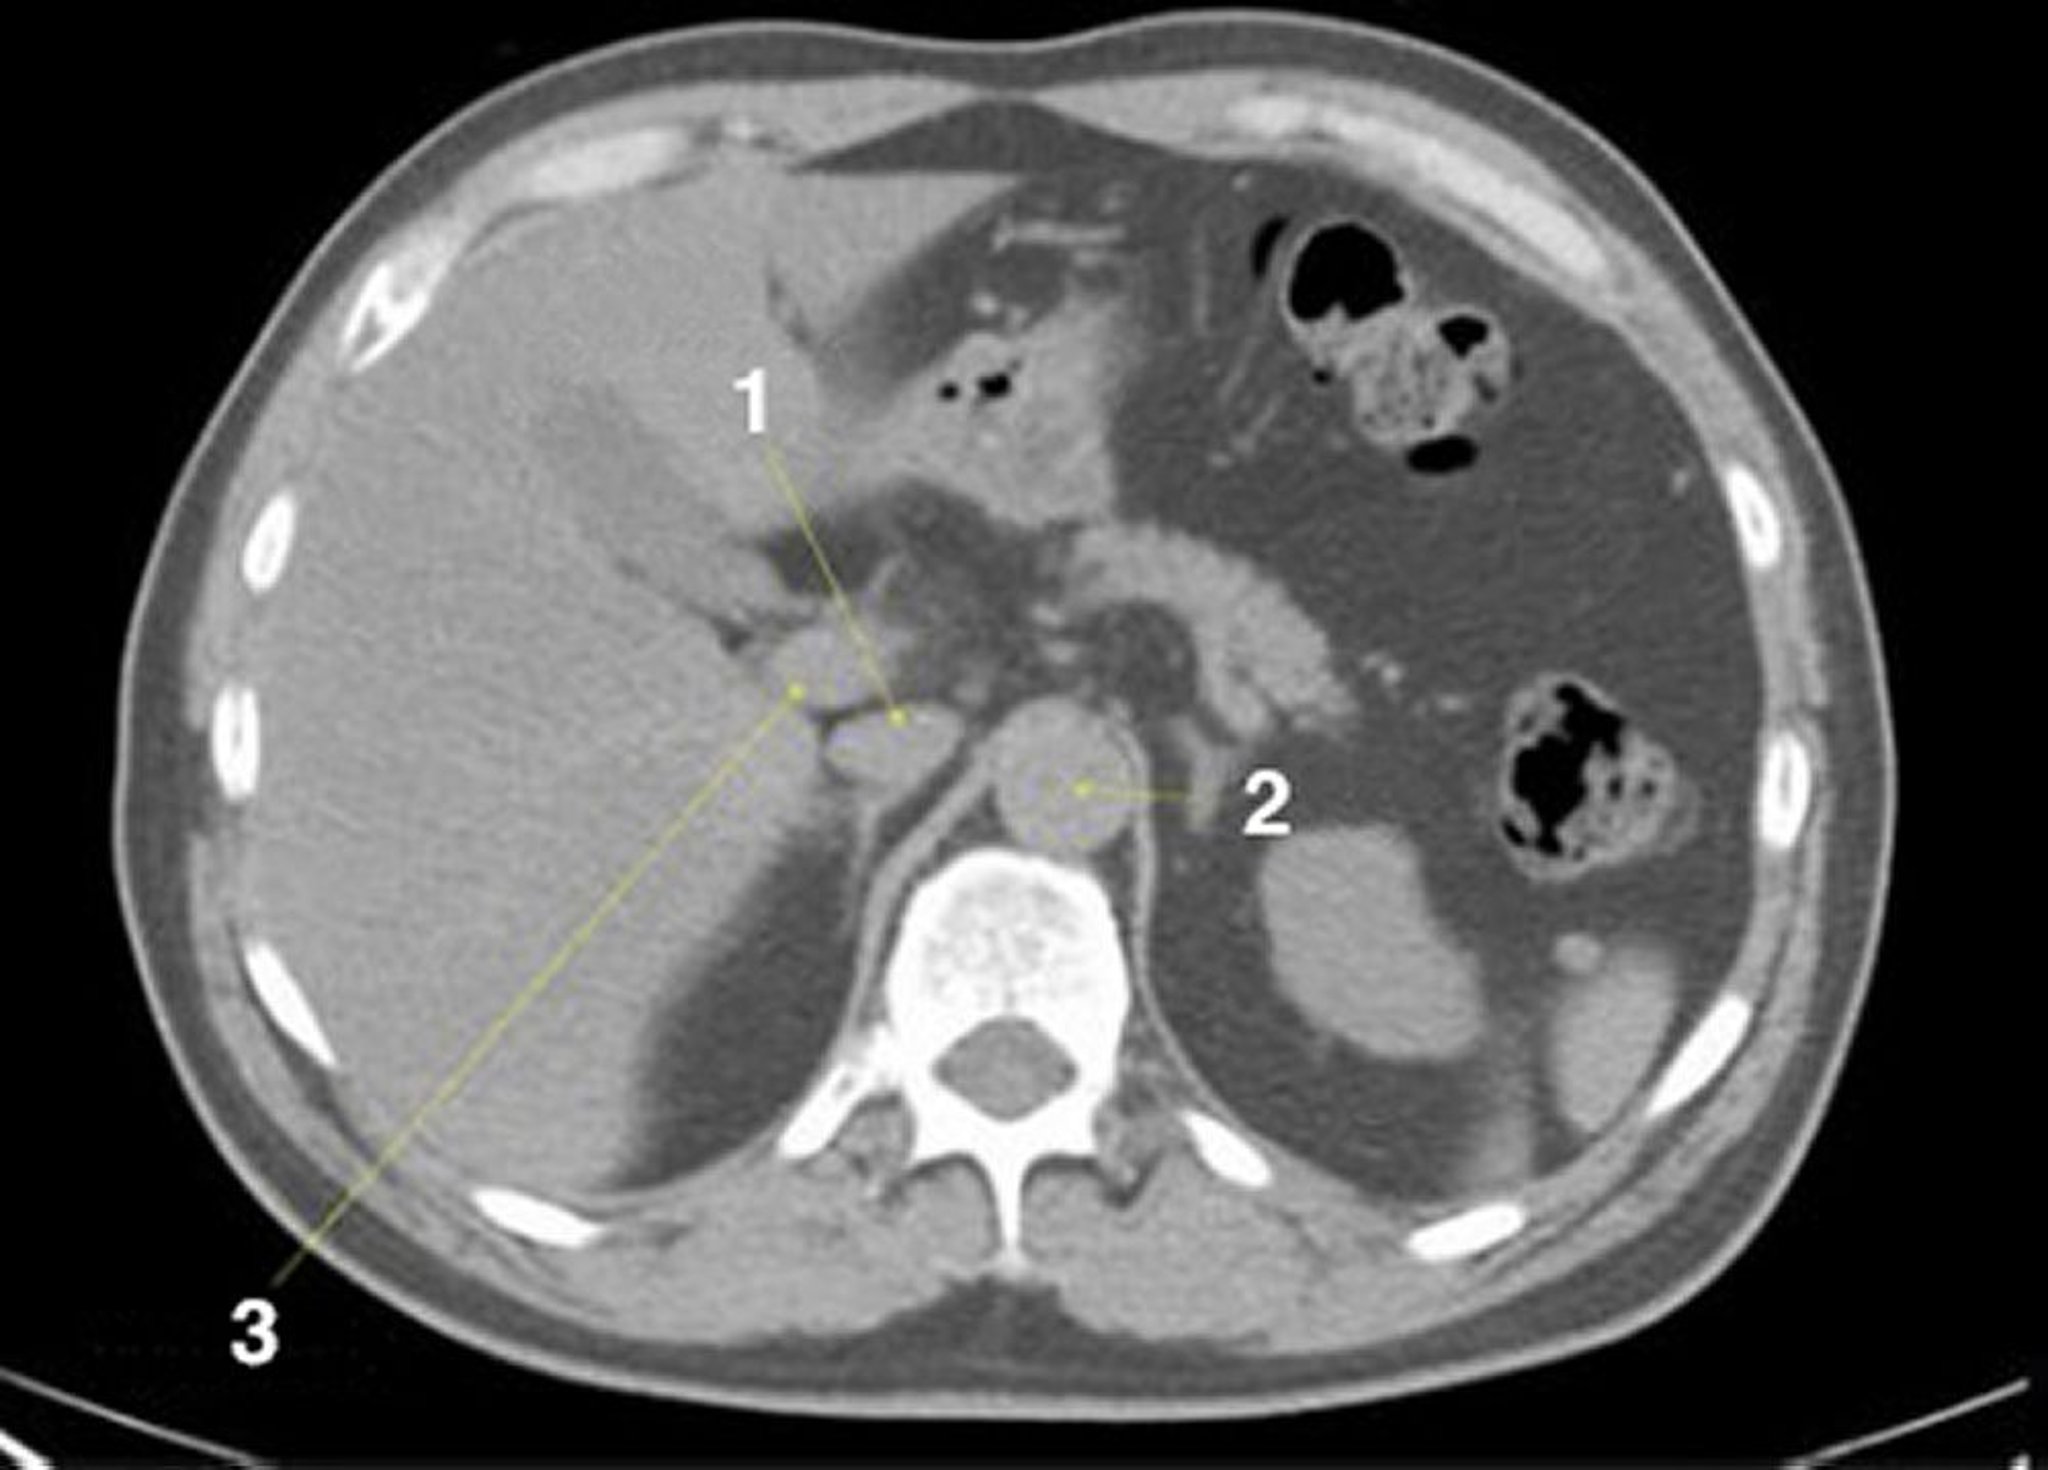

正常解剖を示した腹部および骨盤の単純CT画像(スライド6)

1 = 下大静脈;2 = 大動脈;3 = 門脈。